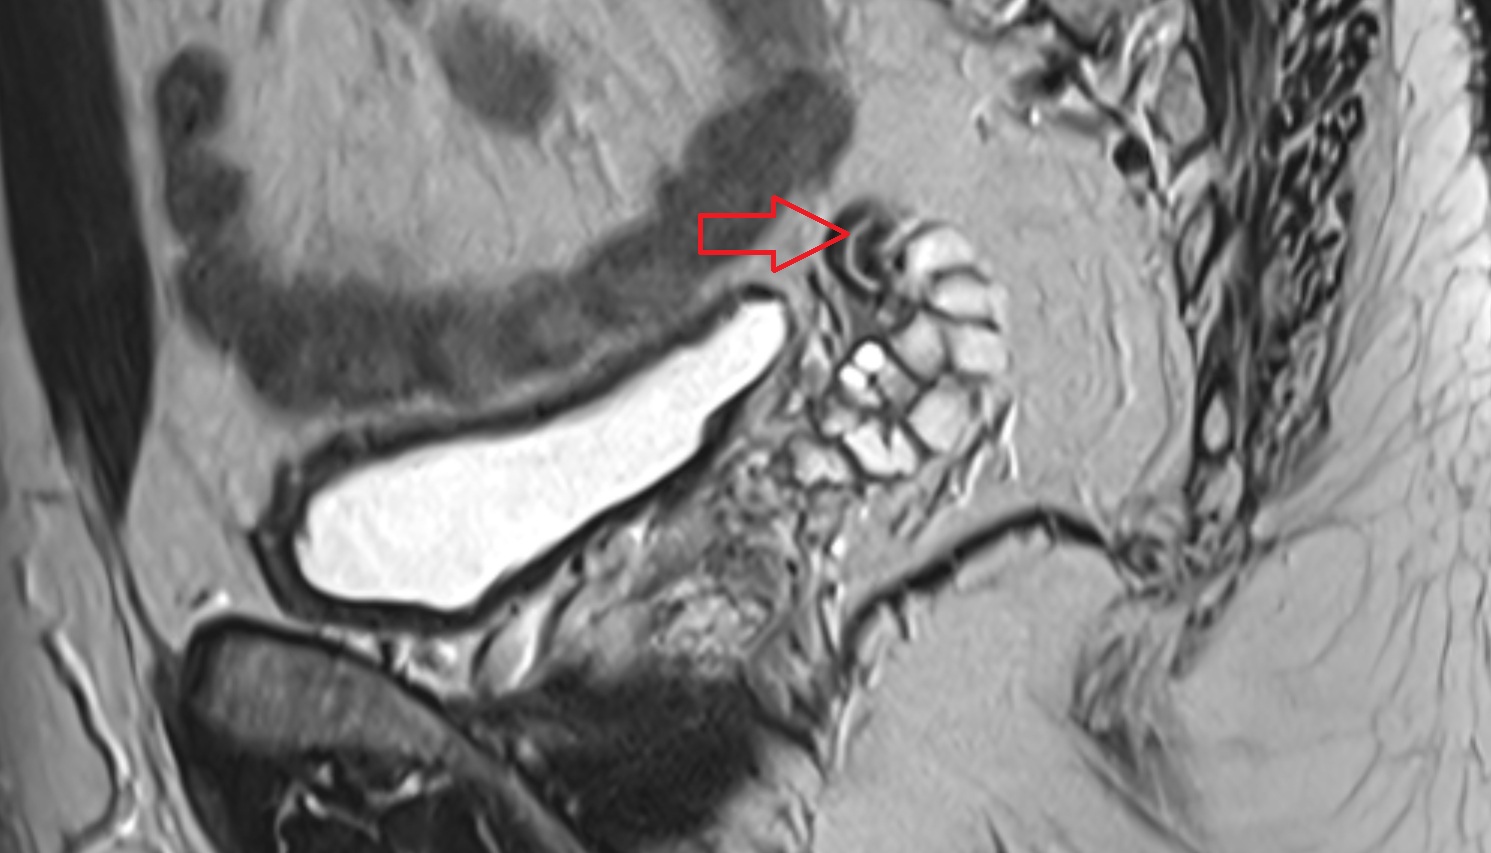

- Uterus

- Cervix of uterus

- Vagina

- Junctional zone of uterus